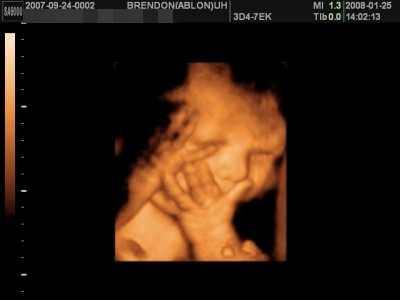

Ativerus, szerintem nyugodtan mond le az időpontot, ide nem érdemes elmenni ezek szerint. Amikor én voltam 15. hetesen( persze más cég, nem ezek a bunkók), ott nagyon rendes volt az ultrahangos nő, és ahhoz képest, hogy még nagyon picike volt akkor a fiam, szuper képeket csinált, és persze egyből látta, hogy kukaca van. Én akkor arra a hétre kaptam időpontot, amikor hívtam őket.

Sokkal szebb képeket csinált, mint amit Anyamci most belinkelt nekünk.Felrakom a kedvencemet, és itt még csak 140 gramm volt a drága

:D

Kép